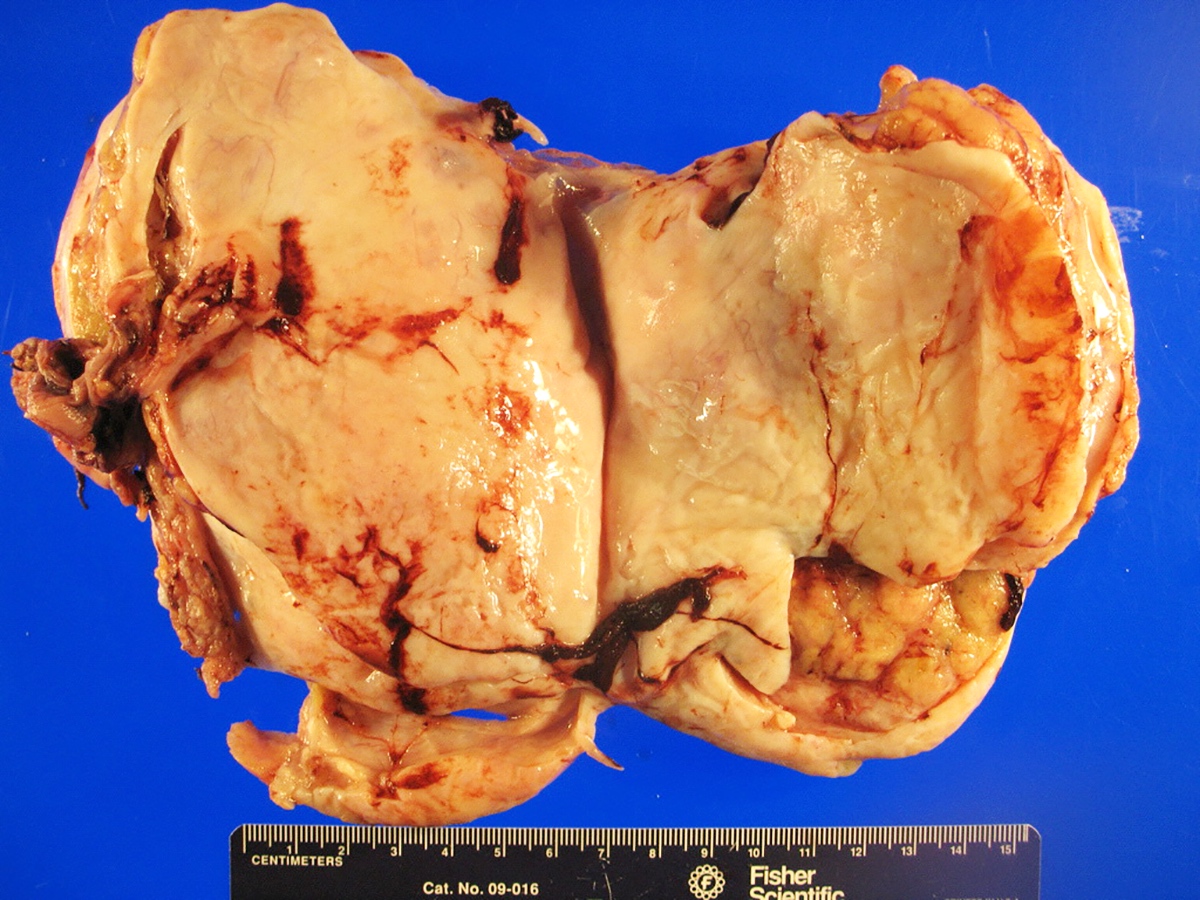

Gross description

- Almost always unilateral (Am J Surg Pathol 1985;9:543)

- Tumor size ranges widely from < 1 cm to 35 cm (mean 12 - 14 cm) (Am J Surg Pathol 1985;9:543)

- Cut surface is typically solid, tan-yellow

- Cystic component may also be seen, especially in tumors with heterologous elements or with a retiform morphologic pattern

- Poorly differentiated tumor may show grossly identifiable foci of necrosis